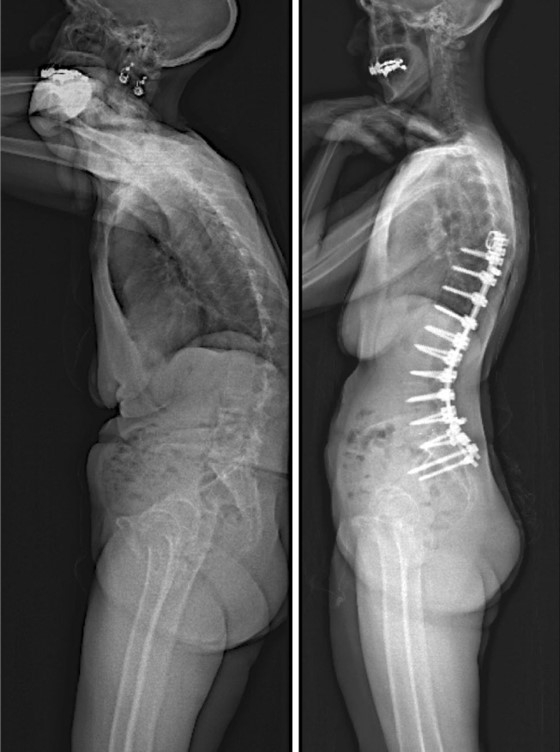

十、PJK和PJF的治疗

PJK无症状者,选择保守治疗,包括观察,支具以及抗骨松治疗等;

PJK存在症状者可行手术治疗。

PJF手术指征:1.内固定失败;2.难以缓解的局部疼痛;3.脊髓神经压迫症状;4.其它因素。

手术策略:1. 如脊柱柔韧性好,可单纯向上延长固定融合;

2.如融合节段上方僵硬,后凸严重,需要截骨。

(1) Smith-Peterson截骨:椎间盘有一定柔韧度,前方无融合;

(2) 三柱截骨(PSO或VCR):严重僵硬畸形,有来自前方的脊髓压迫;

(3)明显的前路缺损(大于50%),需前路支撑。